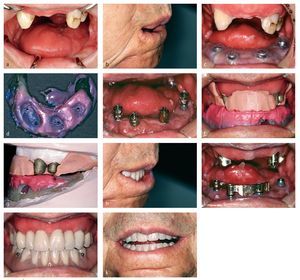

Las hipodoncias congénitas, las cuales pueden aparecer con y sin otros síntomas concomitantes generales, a menudo suelen caracterizarse además por persistencia de la dentición temporal o una forma del diente reducida. En paralelo existen malformaciones de la sustancia dental dura, tanto de la dentina como del esmalte. Pese a las persistentes limitaciones de las tecnologías adhesivas en dientes de leche, así como a las malformaciones de la sustancia dental dura, cada vez con más frecuencia se intenta, siempre y cuando todavía estén presentes suficientes dientes, el uso de prótesis dentales fijas de cerámica sin metal5. Antes del inicio del tratamiento debería llevarse siempre a cabo en el laboratorio dental un encerado que también puede servir para informar al paciente. Sólo con ayuda de un encerado es posible una preparación suficiente, a fin de lograr el resultado funcional y estético más óptimo posible para la mayoría de los pacientes jóvenes (figs. 2a a 3d). El encerado sirve además para la confección de prótesis provisionales tras la preparación.

Fig. 2a. La figura muestra a una paciente de 20 años con hipodoncia congénita en el estado tras un tratamiento previo ortodóncico de varios años, así como aumento óseo vertical y horizontal en las secciones edéntulas del maxilar, antes del inicio del tratamiento protésico con ligera elevación de la mordida. Los puntos de paso de los implantes ponen de manifiesto que el aumento óseo vertical no ha alcanzado el resultado deseado. b Durante el control anual tras el tratamiento protésico mediante supraestructuras de cerámica de silicatos y carillas fijadas adhesivamente en los dientes naturales, así como coronas metalocerámicas en los implantes, la restauración de cerámica sin metal arroja un buen resultado estético. Fue preciso acortar estéticamente la longitud de las coronas de implante en el maxilar superior mediante la cocción de cerámica de color rosa. c Pese a la sonrisa cervical de la paciente, puede considerarse el resultado como suficientemente satisfactorio (prótesis dental: Rolf Bachmann).

Fig. 3a. Esta paciente de 17 años padece una hipodoncia, persistencia de la dentición temporal en ambos caninos superiores, así como una forma generalmente reducida de todos los dientes permanentes. Esto da lugar a una relación maxilar vertical demasiado baja y a un leve subdesarrollo del tercio medio del rostro, lo cual requiere una considerable elevación de la mordida. b La imagen lateral muestra claramente que el labio superior no está bien apoyado debido a los dientes reducidos y a las agenesias. Las modificaciones de la posición mediante ortodoncia no pudieron solucionarlo. c En el frente superior se ha colocado un puente anterior continuo desde el diente 53 hasta el 63. En la zona de los dientes posteriores fue preciso confeccionar coronas parciales para la elevación de la mordida en los maxilares superior e inferior, y carillas en el frente inferior. Por motivos de estabilidad se utilizaron estructuras de cerámica de disilicato de litio comprimidas, completamente recubiertas en el frente superior, recubiertas sólo por incisal en las carillas y únicamente pintadas en la zona de los dientes posteriores. Toda la reposición dental está fijada adhesivamente (prótesis: protésico dental Rolf Bachmann). d Con la prótesis dental colocada mejoran el perfil de los labios y la altura del tercio inferior del rostro. Debido a los años de disfunción y a la tendencia a la parafunción, es recomendable colocar una férula de descarga o un aparato de retención ortodóncico en el maxilar en el que puedan aparecer antes migraciones dentales. En caso de que desempeñen un papel las disfunciones de la lengua, son necesarios ejercicios logopédicos a continuación de la rehabilitación intraoral.

Sin embargo, en caso de que falten demasiados dientes, las restauraciones protésicas implantológicas constituyen el medio de elección. Dado que, en caso de hipodoncia congénita, no se forman los procesos alveolares, el hueso disponible reducido requiere habitualmente un aumento de las áreas a implantar. Si bien a menudo resulta posible una buena reconstrucción de la cresta alveolar en anchura, la reconstrucción vertical presenta grandes dificultades y en ocasiones sólo se consigue un compromiso (figs. 2a a 2c y 4a a 4d).

Fig. 4a. Esta paciente de 25 años con agenesias desde el 34 hasta el 47 fue tratada con siete implantes en un segundo paso tras un aumento transversal con cresta iliaca libre. Pese a la plantilla de taladrado, en ocasiones un espacio disponible reducido obliga a insertar los implantes en una posición no ideal protésicamente. b Durante la prueba de cera en boca antes de la confección de la estructura para un puente fijo puede apreciarse claramente que la paciente mostrará las papilas en el maxilar inferior. Por lo tanto, será preciso simular éstas mediante cerámica rosa. c Mediante electroerosión por chispas se libera de tensiones el puente sobre un modelo especialmente confeccionado. Previamente tuvo lugar un nuevo registro de los implantes en boca mediante fijación de los postes de impresión y utilizando un poco de material autopolimerizable contraíble después de la cocción de la cerámica sobre los pilares originales. d Se coloca el puente con cemento provisional. Si los implantes no se encontraran en cierta medida bajo los dientes a reponer, peligraría la colocación de un puente fijo. Sin embargo, la imagen muestra de nuevo claramente que es muy difícil alcanzar quirúrgicamente un restablecimiento óptimo de una línea de recorrido papilar natural (prótesis: protésico dental Rolf Bachmann).